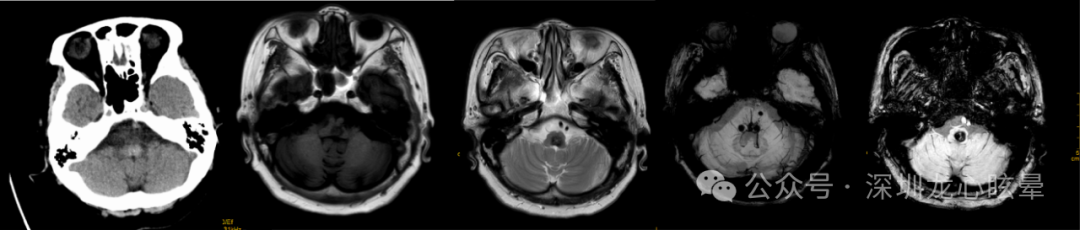

CVIV 大多为供应小脑和脑干的椎-基底动脉系统缺血或出血性病变所致,而以脑梗死最为多见。小脑出血引起的血管源性头晕/眩晕:小脑出血多表现为严重急性眩晕发作,伴头痛、恶心呕吐及严重姿势平衡障碍,大约50%的患者在发病24 h内意识丧失,75%的患者在发病1周内昏迷。脑干出血引起的血管源性头晕/眩晕:脑桥大量出血者初始症状可表现为眩晕、头痛及呕吐,症状进展可导致四肢瘫、去脑强直、异常水平眼动、眼球浮动、针尖样瞳孔乃至昏迷;原发性延髓出血较为少见,表现为突发性眩晕、头痛、恶心呕吐及吞咽构音障碍,严重者可出现心肺功能衰竭。动静脉畸形所致的脑出血则影像学表现相对重,而症状轻微。颅脑CT影像学检查是快速识别小脑/脑干出血最有效的方法。

图1 一例小脑出血